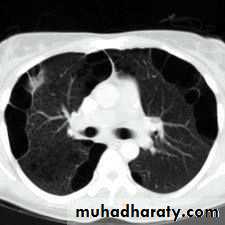

Loculated pleural effusion or empyema

History: dyspnea, weight loss, dehydration with poor immunity